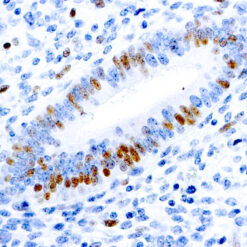

TNF-alpha (Tumor Necrosis Factor alpha)

This MAb recognizes human 17-26kDa protein, which is identified as cytokine TNF-α (Tumor Necrosis Factor-alpha). Monomeric human TNF-α is a 157 amino acid protein (non-glycosylated) with a reported molecular weight of 17 kDa and can be expressed as a free molecule, also TNF-α is generated as a precursor form called transmembrane TNF-α can be expressed as a cell surface type II polypeptide consisting of 233 amino acid residues molecular weight 26 kDa. TNF-α is an important cell-signaling component of the immune system. It is a protein secreted by LPS stimulated macrophages, and causes tumor necrosis when injected into tumor bearing mice. TNF-α is currently being evaluated in treatment of certain cancers and AIDS Related Complex.

| Positive Control Tissue | Colon, Histiocytoma, Pancreas |